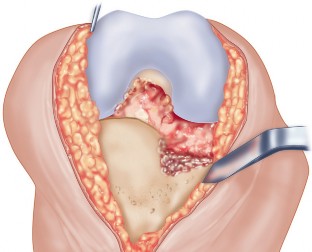

الشق الجراحي:

يُستخدم شق طولي في الجانب الإنسي (الداخلي) من الركبة. يجب أن يكون الشق كبيرًا بما يكفي لتوفير رؤية جيدة للمفصل الرضفي الفخذي وإمكانية التحويل إلى TKA.

- فتح المفصل (Arthrotomy): يكون الفتح خطيًا وموازياً لألياف الوتر الرضفي، ويمتد إلى عظم الظنبوب وإلى الجزء السفلي من الرضفة.

- تحرير الأنسجة الرخوة: يتم قطع الغضروف الهلالي لتحرير الأنسجة الرخوة من عظم الظنبوب، ويتم تطوير سديلة تحت السمحاق في نمط دائري حول الظنبوب. يُمدد هذا التحرير خلفيًا لضمان توازن الأربطة.

-

تصحيح التشوه:

الهدف هو تحقيق تصحيح طفيف للتشوه، مع وجود رخاوة كاذبة طفيفة عند تطبيق ضغط تفحجي في نهاية الإجراء. يجب تجنب التصحيح المفرط.